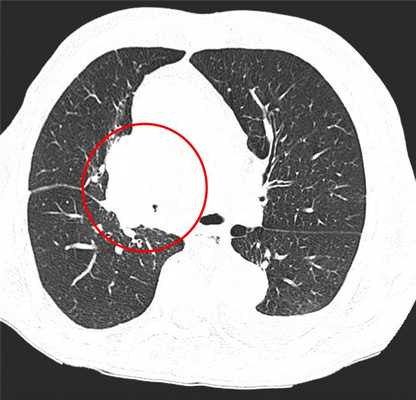

КТ-признаки центрального рака легкого: при компьютерной томографии определяется объемное образование мягкотканной структуры, в котором «обрывается» просвет нижнедолевого бронха. Края образования бугристые, неровные, со спикулами, форма неправильная.

Центральный рак легкого на КТ. Обратите внимание на различия в ширине просвета центральных бронхов справа и слева. Просвет правого верхнедолевого бронха не виден. Виден ателектаз верхней доли. В круге - непосредственно само опухолевое образование, ставшее причиной ателектаза.

Периферический рак легких на КТ выглядит как очаг либо узел, расположенный на периферии органа вдалеке от корня. Обычно он имеет однородную структуру, в некоторых случаях с участками некроза, обызвествлениями и кровоизлияниями в паренхиму. Края типичной раковой опухоли неровные, с множественными «спикулами» за счет лимфангиита. При расположении вблизи плевры образование деформирует ее и подтягивает к себе. Размеры его различны - от очага (3-10 мм) до узла (10-50 мм и больше).

Типичный периферический рак легкого (аденокарцинома) на МСКТ. Справа в 6 сегменте легкого выявлен плотный мягкотканный узел со спикулами, деформирующий и подтягивающий к себе междолевую плевру.